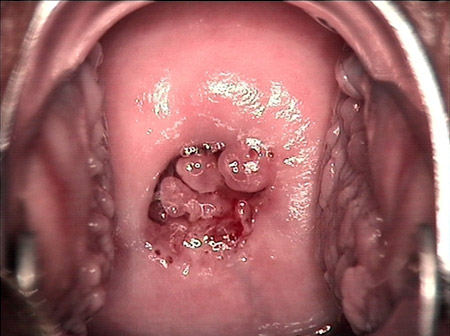

婦科leep錐切手術(shù) CIN2-3

• CIN 2-3CIN 2-3